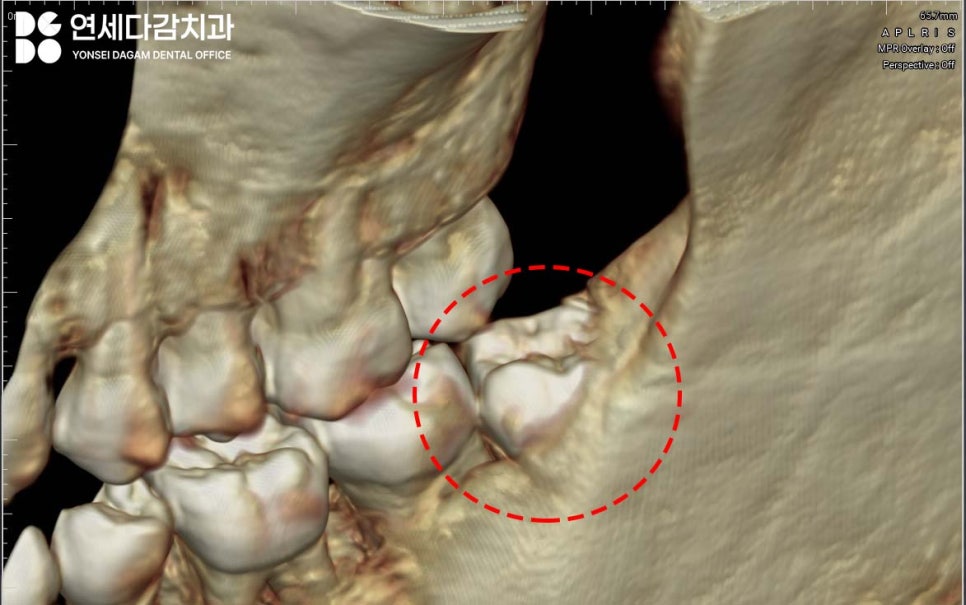

이럴 때 CBCT 촬영이 필요합니다.

CT는 3차원 입체 영상으로

신경관과 치아 뿌리의 위치 관계를

정밀하게 보여줍니다.

가락동 치과 에서는 사랑니를 진단할 때

CT를 필수로 촬영해서

안전한 발치 계획을 세우게 됩니다.

CT를 확인해 보면

치아의 일부가 뼈 속에 묻혀있는

경우가 있습니다.

특히 치아의 뒤쪽 부분이

치조골에 갇혀있으면

위로 당겨서 빼는 것이 불가능합니다.